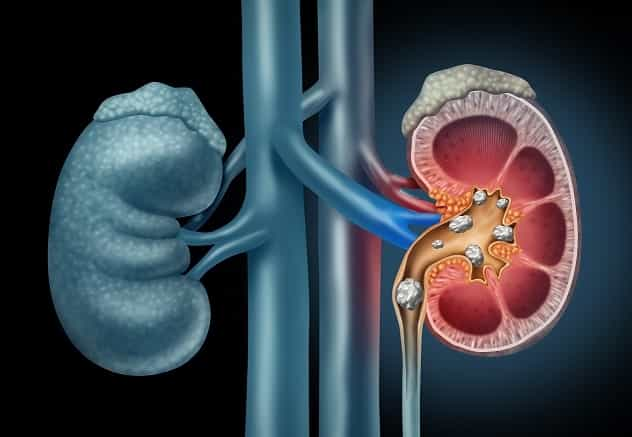

Neeruhaiguse tunnused ja sümptomid.

Krooniline neeruhaigus jaguneb etappideks 1-5, mis vastavad neeruhaiguse raskusastmele. Enamikul inimestel ei ole neeruhaiguse sümptomeid enne, kui kahjustus on väga…